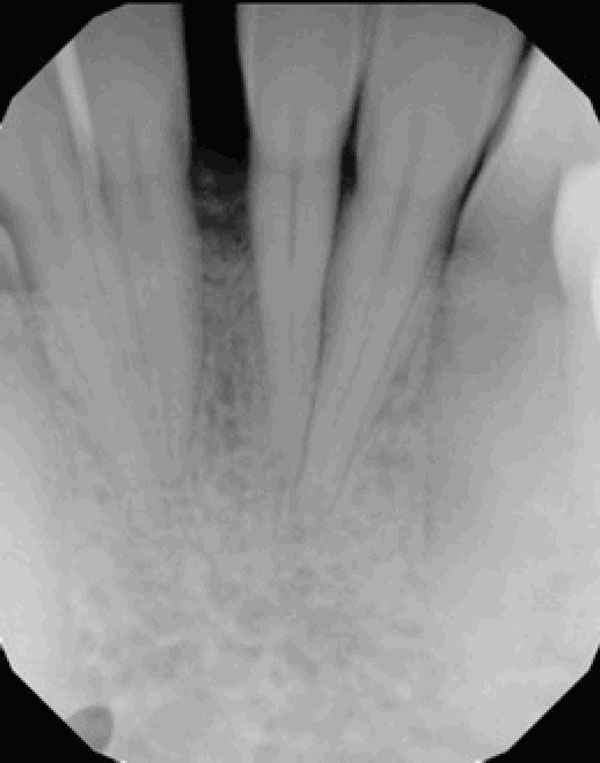

Clinical examination revealed the space formation between teeth 24 and 25 (Fig. 1a). The overlying mucosa and gingiva appeared normal in color. Deep probing elicited bleeding from the problem site. Radiographic evaluation revealed a well-circumscribed, low-density, radiolucent lesion between the mandibular central incisors, with spacing between teeth 24 and 25 (Fig. 1b) as well as thinning and expansion of the buccal and lingual cortical plates (Figs. 1c-1e). No other pathology was detected by the oral and maxillofacial radiologist on the images.

Fig. (1b).

Radiograph suggests vertical bone loss and separation of teeth 24 and 25.

Severe vertical bone loss is evident on this image of mandibular central incisors.